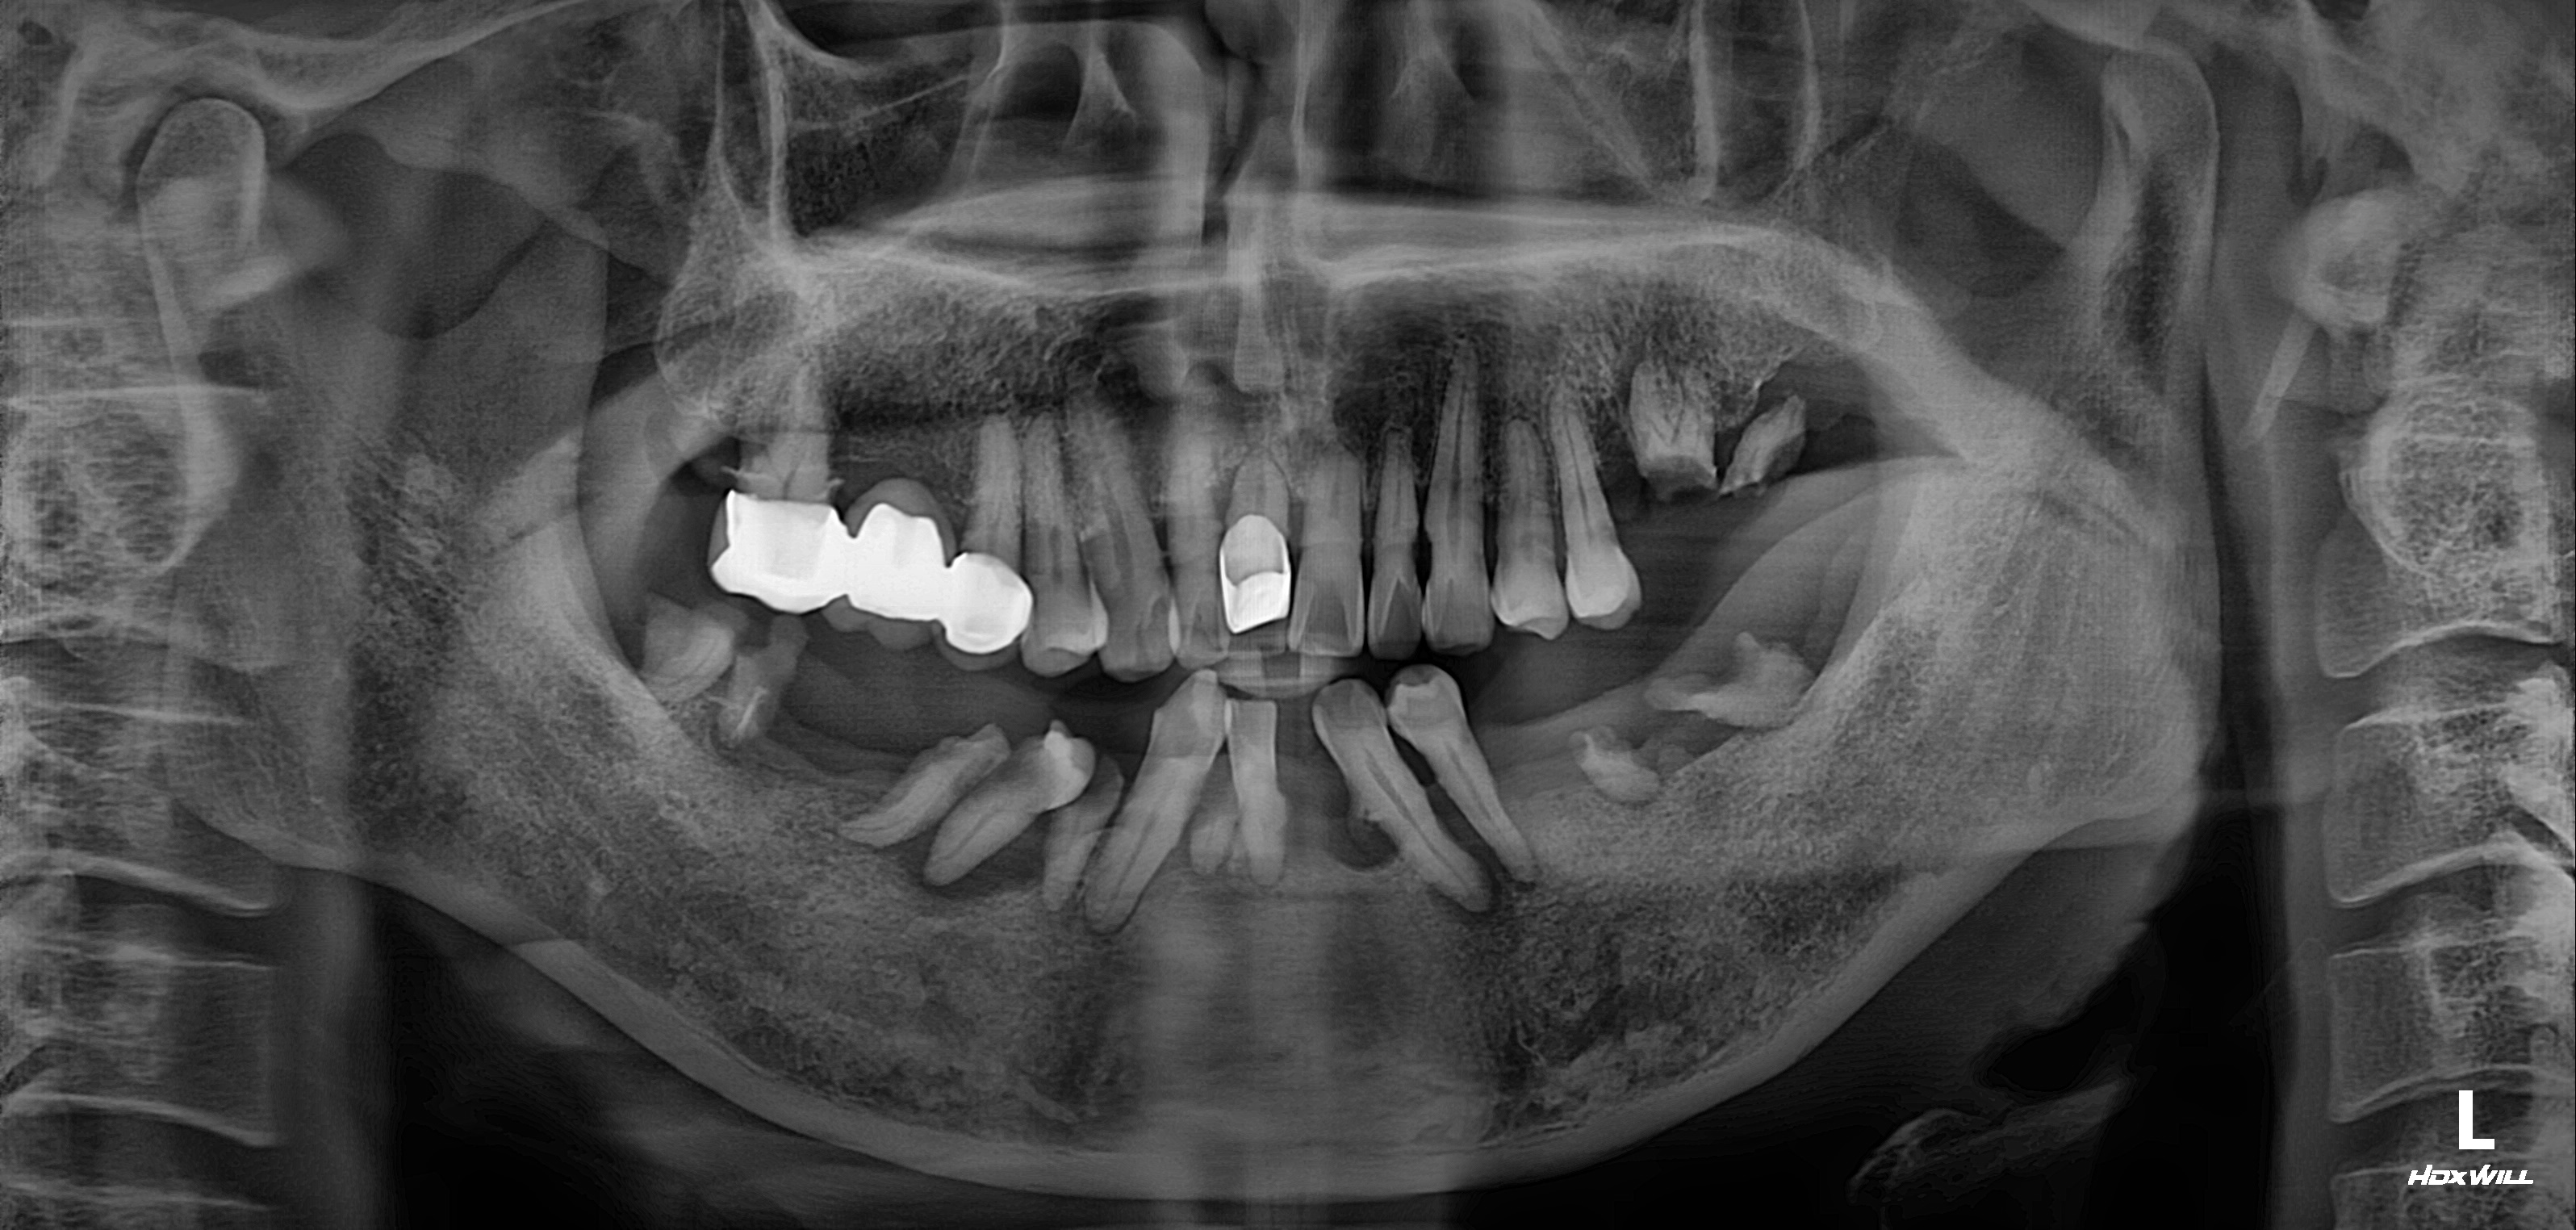

하악 전체+상악 부분 임플란트 식립사례